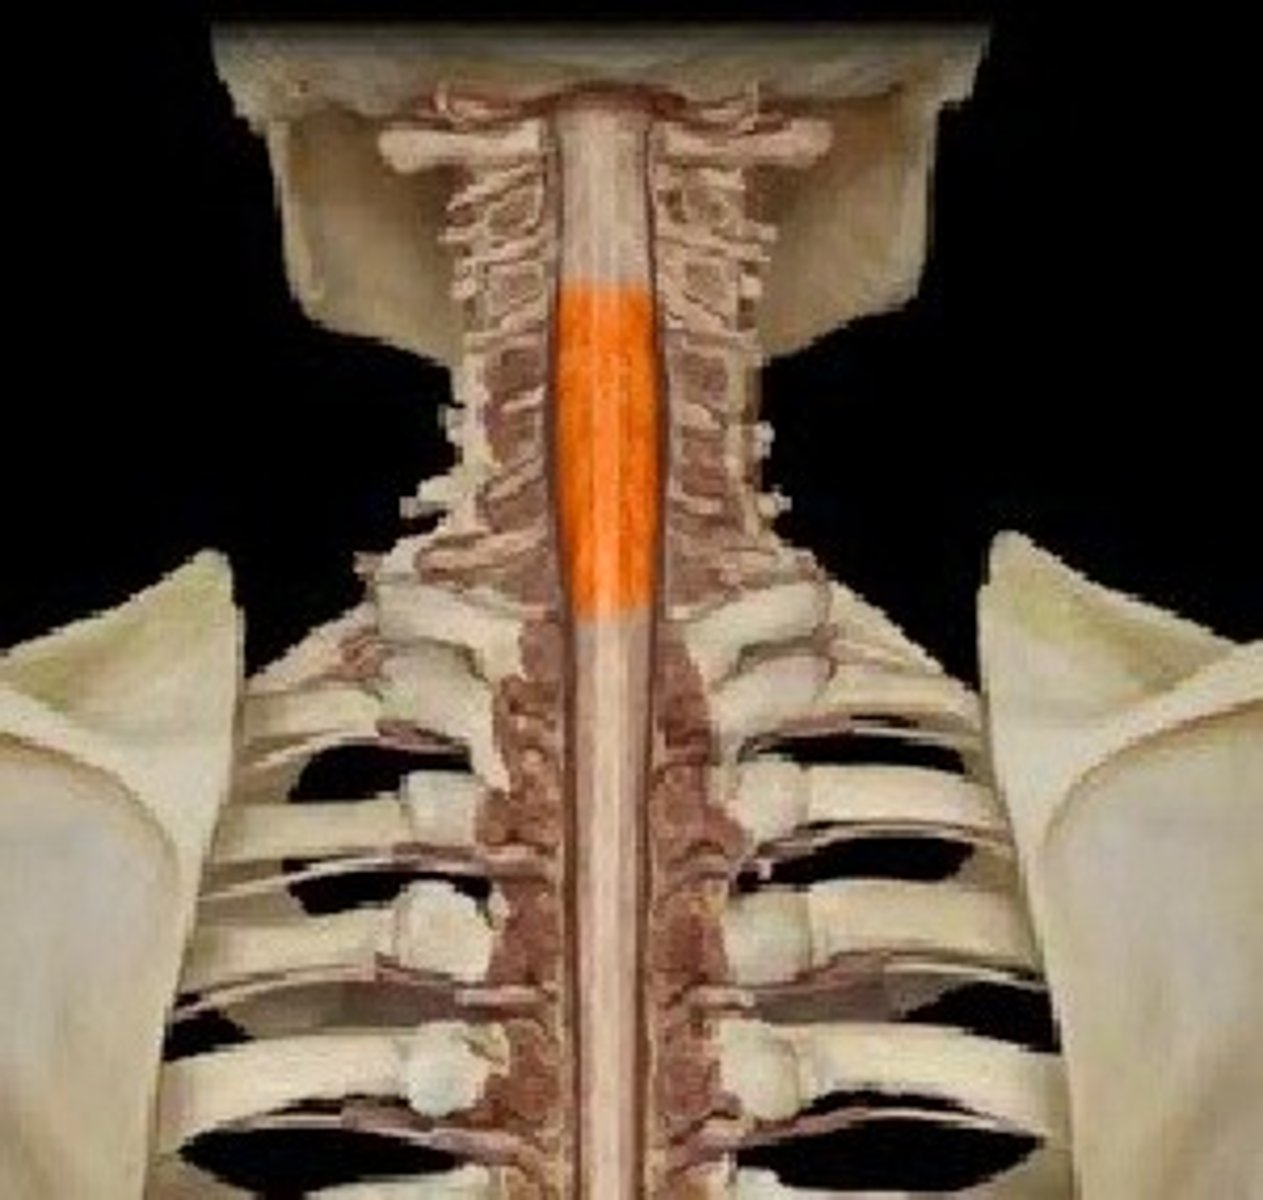

cervical enlargement